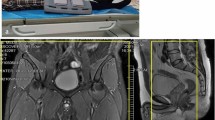

The femoral vein occlusion by thrombus was identified in all cases on NC-MRV and matched the ultrasound findings for location and extent. The thrombus length was between 6.4 and 40.0 cm (mean 27.7 cm) on the first visit. On visit 2, thrombus was no longer present in 4/13 cases, had reduced in length in a further 6/13 cases (range 3.8–30.3 cm, mean 15.9 cm) and was unchanged in the remaining three cases (range 32.4–39.0 cm). On visit 3, only 6/13 cases still had thrombus present (range 17.9–39.0 cm, mean 30.4 cm). Figures 1 (patient G) and 2 (patient C) show NC-MRV and MR-DTI images in two patients with venous occlusion on all three visits, while Fig. 3 shows the measured lengths of the occluded region on the NC-MRV and the corresponding MR-DTI images for each visit and each patient. All thrombus length measurements are summarized in Table 1.

Images for an example patient showing the evolution of the thrombus signal. The NC-MRV image (a composite MIP from the two table positions) shows an occluded right femoral vein at all three time-points, but the thrombus is visible on MR-DTI only for the first examination. MR-DTI images are shown as curved-plane reformats

On the first visit, high signal at MR-DTI was found to match spatially the NC-MRV-defined occlusion in all but one case. This exception case (patient I) is shown in Fig. 4 and is discussed below. On the subsequent second and third visits, the thrombus was either not visualized or only small/fragmented bright signal areas were seen on MR-DTI—less than 29 % (visit 2) and 3 % (visit 3) of the original thrombus length. The case with most residual bright thrombus signal on visits 2 and 3 is shown in Fig. 5 (patient L). Recanalisation, as assessed on the NC-MRV images, occurred in seven patients, but in six patients the superficial femoral vein remained partially or completely occluded.

Our study is in line with previous work and confirms the potential value of MR-DTI in the diagnosis and follow-up of acute DVT involving the femoral and proximal popliteal veins by detecting the presence and changes in methaemoglobin content of the recently formed thrombus [18]. It demonstrates that by 3 months from the thrombotic event about a third of the thrombi had resolved and by 6 months only about half of the cases had residual thrombus present. When following the evolution of methaemoglobin changes over time, at 3 months less than half of the patients showed persistent, albeit small and fragmented, hyperintense areas at the site of the thrombus that almost completely cleared at the 6-month MR-DTI examination, consistent with the expected evolution of methaemoglobin.

The length and location of the thrombus matched in all patients on the NC-MRV and MR-DTI images on the first visit, except in one case (patient I shown in Fig. 4). In this patient, the proximal and distal ends of the thrombus were clearly depicted on both the NC-MRV and MR-DTI images, but the MR-DTI signal was discontinuous distally in the region of the knee. However, the extent of thrombus could still be reliably measured, as an absence of flow was demonstrated in the region of MR-DTI discontinuity.

Figure 5 (patient L) shows persistent occlusion of the vein on all 3 visits with multiple short discontinuous hyperintense segments remaining at 3 months (visit 2) and reducing substantially in size at 6 months (visit 3). At visit 2, this exam contains the most high signal MR-DTI fragments of any examination in this study. These fragments are discontinuous and are more likely to represent residual fragmented thrombi from the initial thrombotic event, as the vein remained completely occluded (confirmed by the NC-MRV) and the bright foci were located more centrally in the vein as opposed to the peripheral “ring-like” distribution of the bright signal on the surface of the thrombus at visit 1.